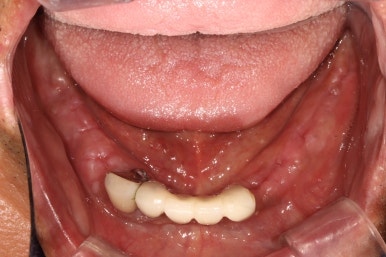

정면에서 찍은 구강 내 사진입니다.

대부분의 치아가 크라운으로 씌워져 있으셨어요. 아무래도 보철물이 너무 많다보니, 구강위생관리가 쉽지 않으신 상태였습니다.

최대한 가성비 있는 치료를 원하셨고, 살릴 수 있는 치아 및 크라운은 남겨두고 싶어 하셨어요.